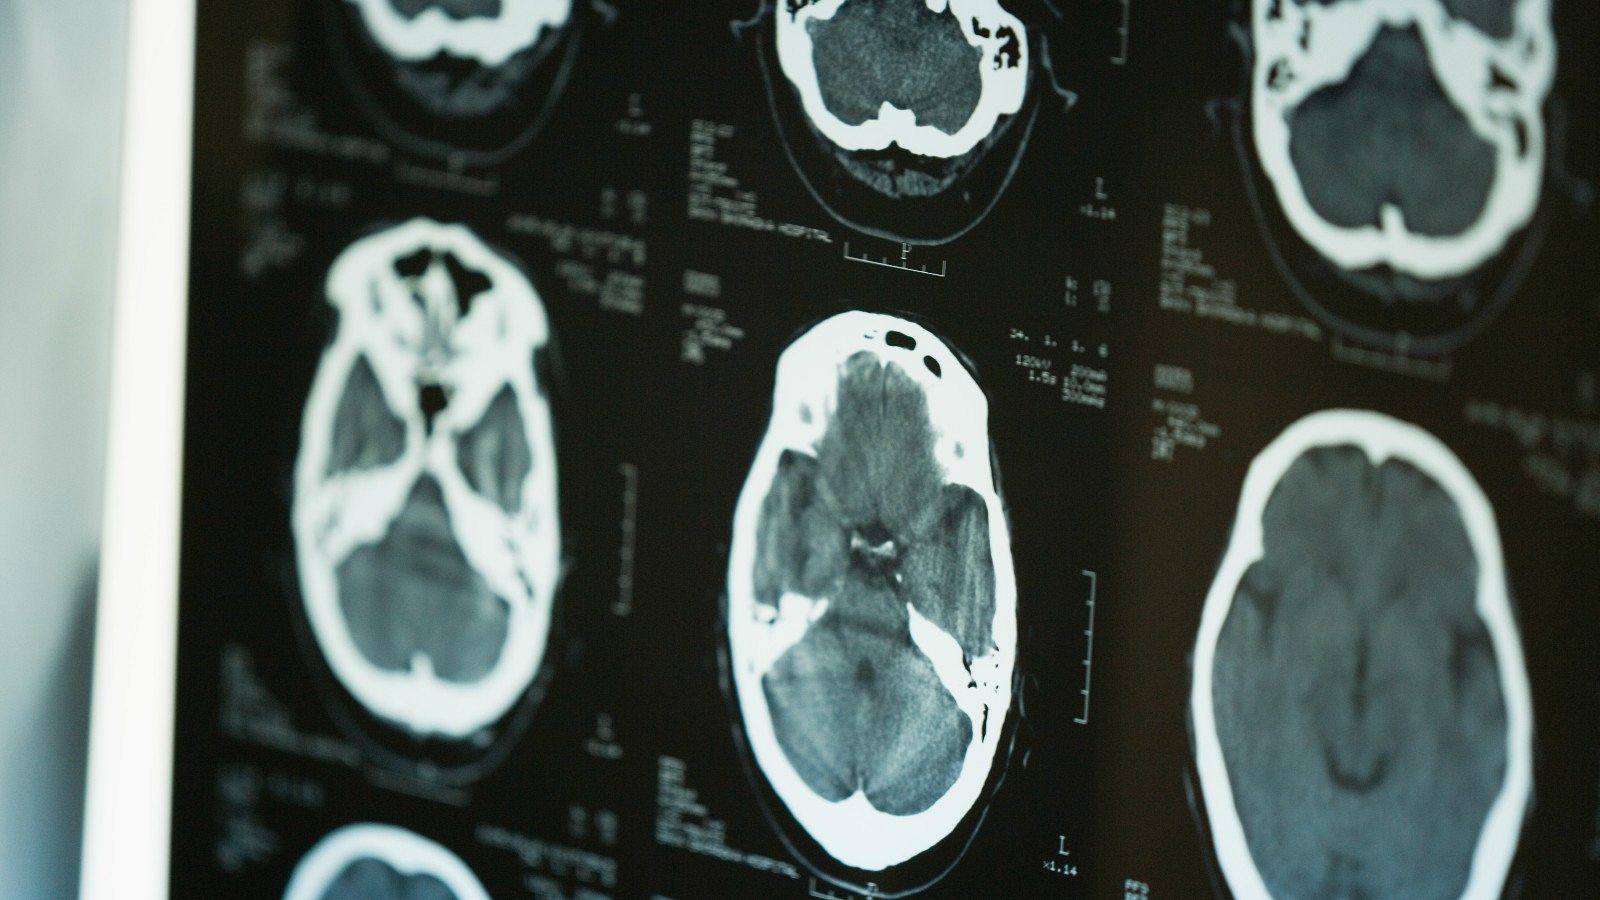

Neus lleva más de 20 años conviviendo con la esclerosis múltiple. "Hay muchas cosas que no puedes hacer. Ya no trabajo, soy pensionista", cuenta a un equipo de TVE, sobre una enfermedad que le ha causado problemas de movilidad y se manifiesta de "forma diferente a cada una de las personas". El origen de esta enfermedad neurodegenerativa, que afecta a unas 50.000 personas en España, es desconocido, pero desde este jueves sabemos un poco más.

Durante dos décadas, científicos de la Universidad de Harvard han hecho seguimiento de los 10 millones de militares estadounidenses. De los 801 soldados diagnosticados de esclerosis múltiple, todos menos uno habían sido infectados con el virus de Epstein Barr, según la investigación publicada en la revista Science. Así, los autores de la investigación señalan que la infección de mononucleosis multiplicaría por 32 el riesgo de padecer esclerosis múltiple. La noticia abre una ventana a la esperanza para neurólogos y pacientes, que todavía prefieren ser cautelosos.